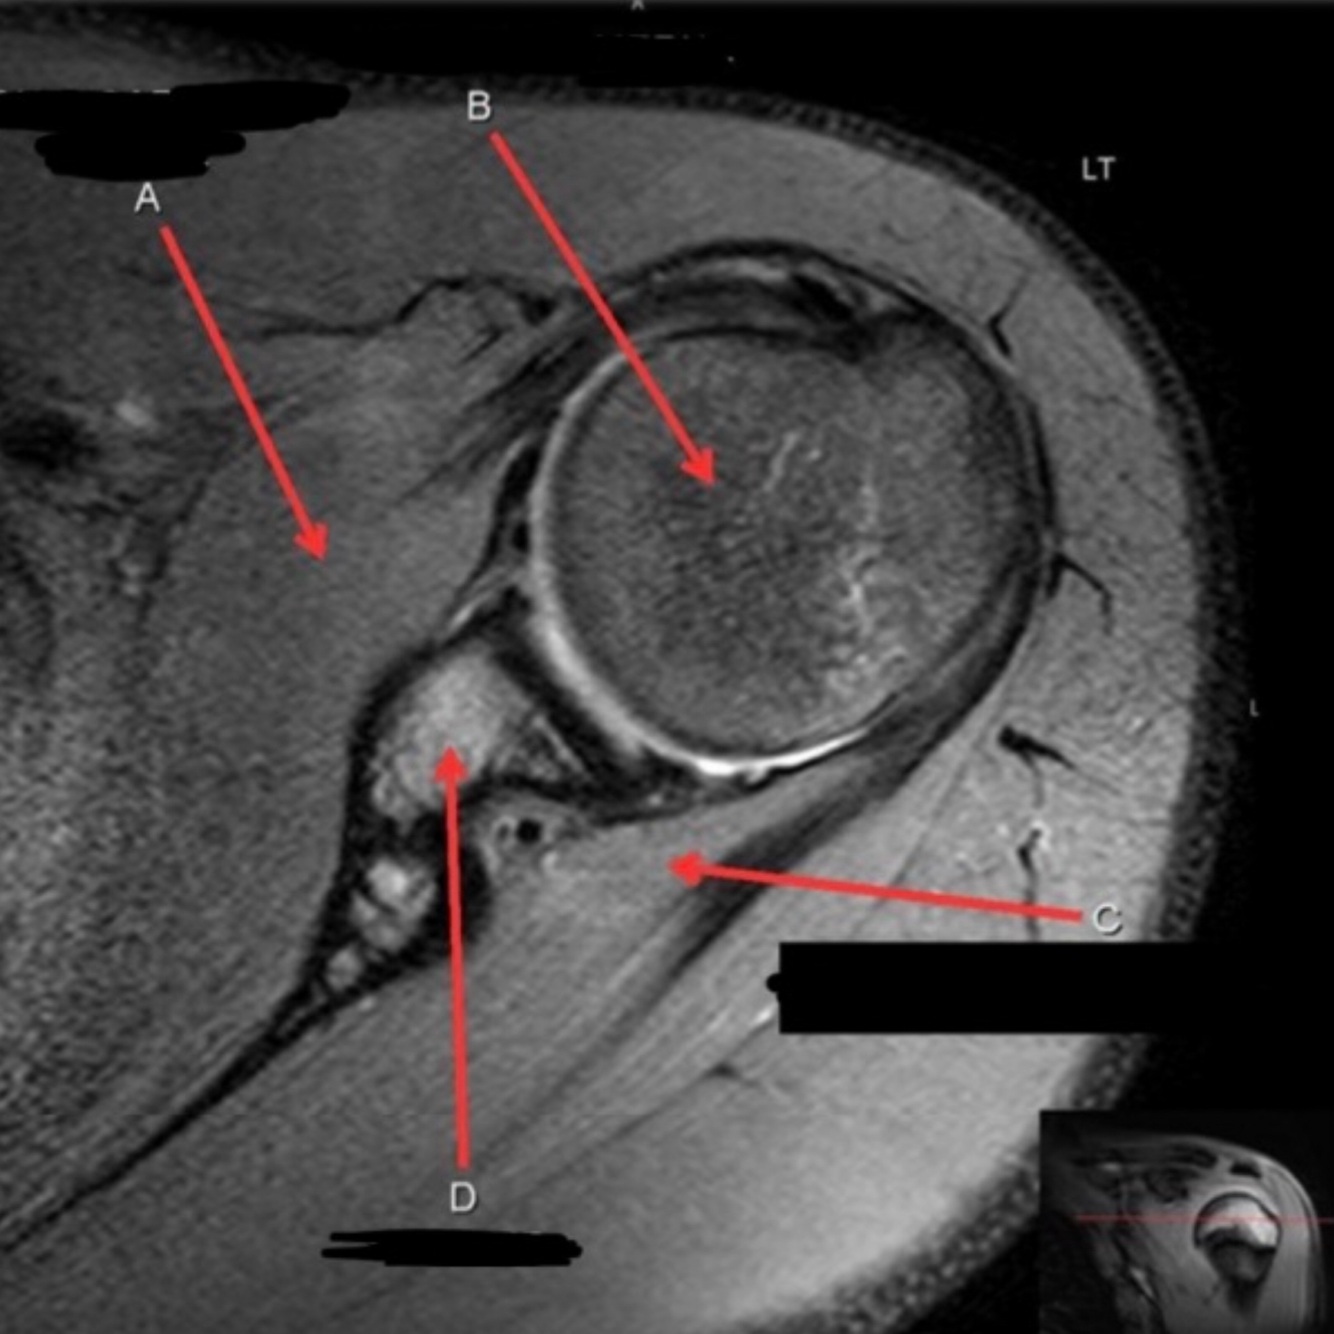

What is letter A?

A

SUBSCAPULARIS MUSCLE

Q

What is letter B?

What is letter C?

INFRASPINATUS MUSCLE

What is letter D?

GLENOID